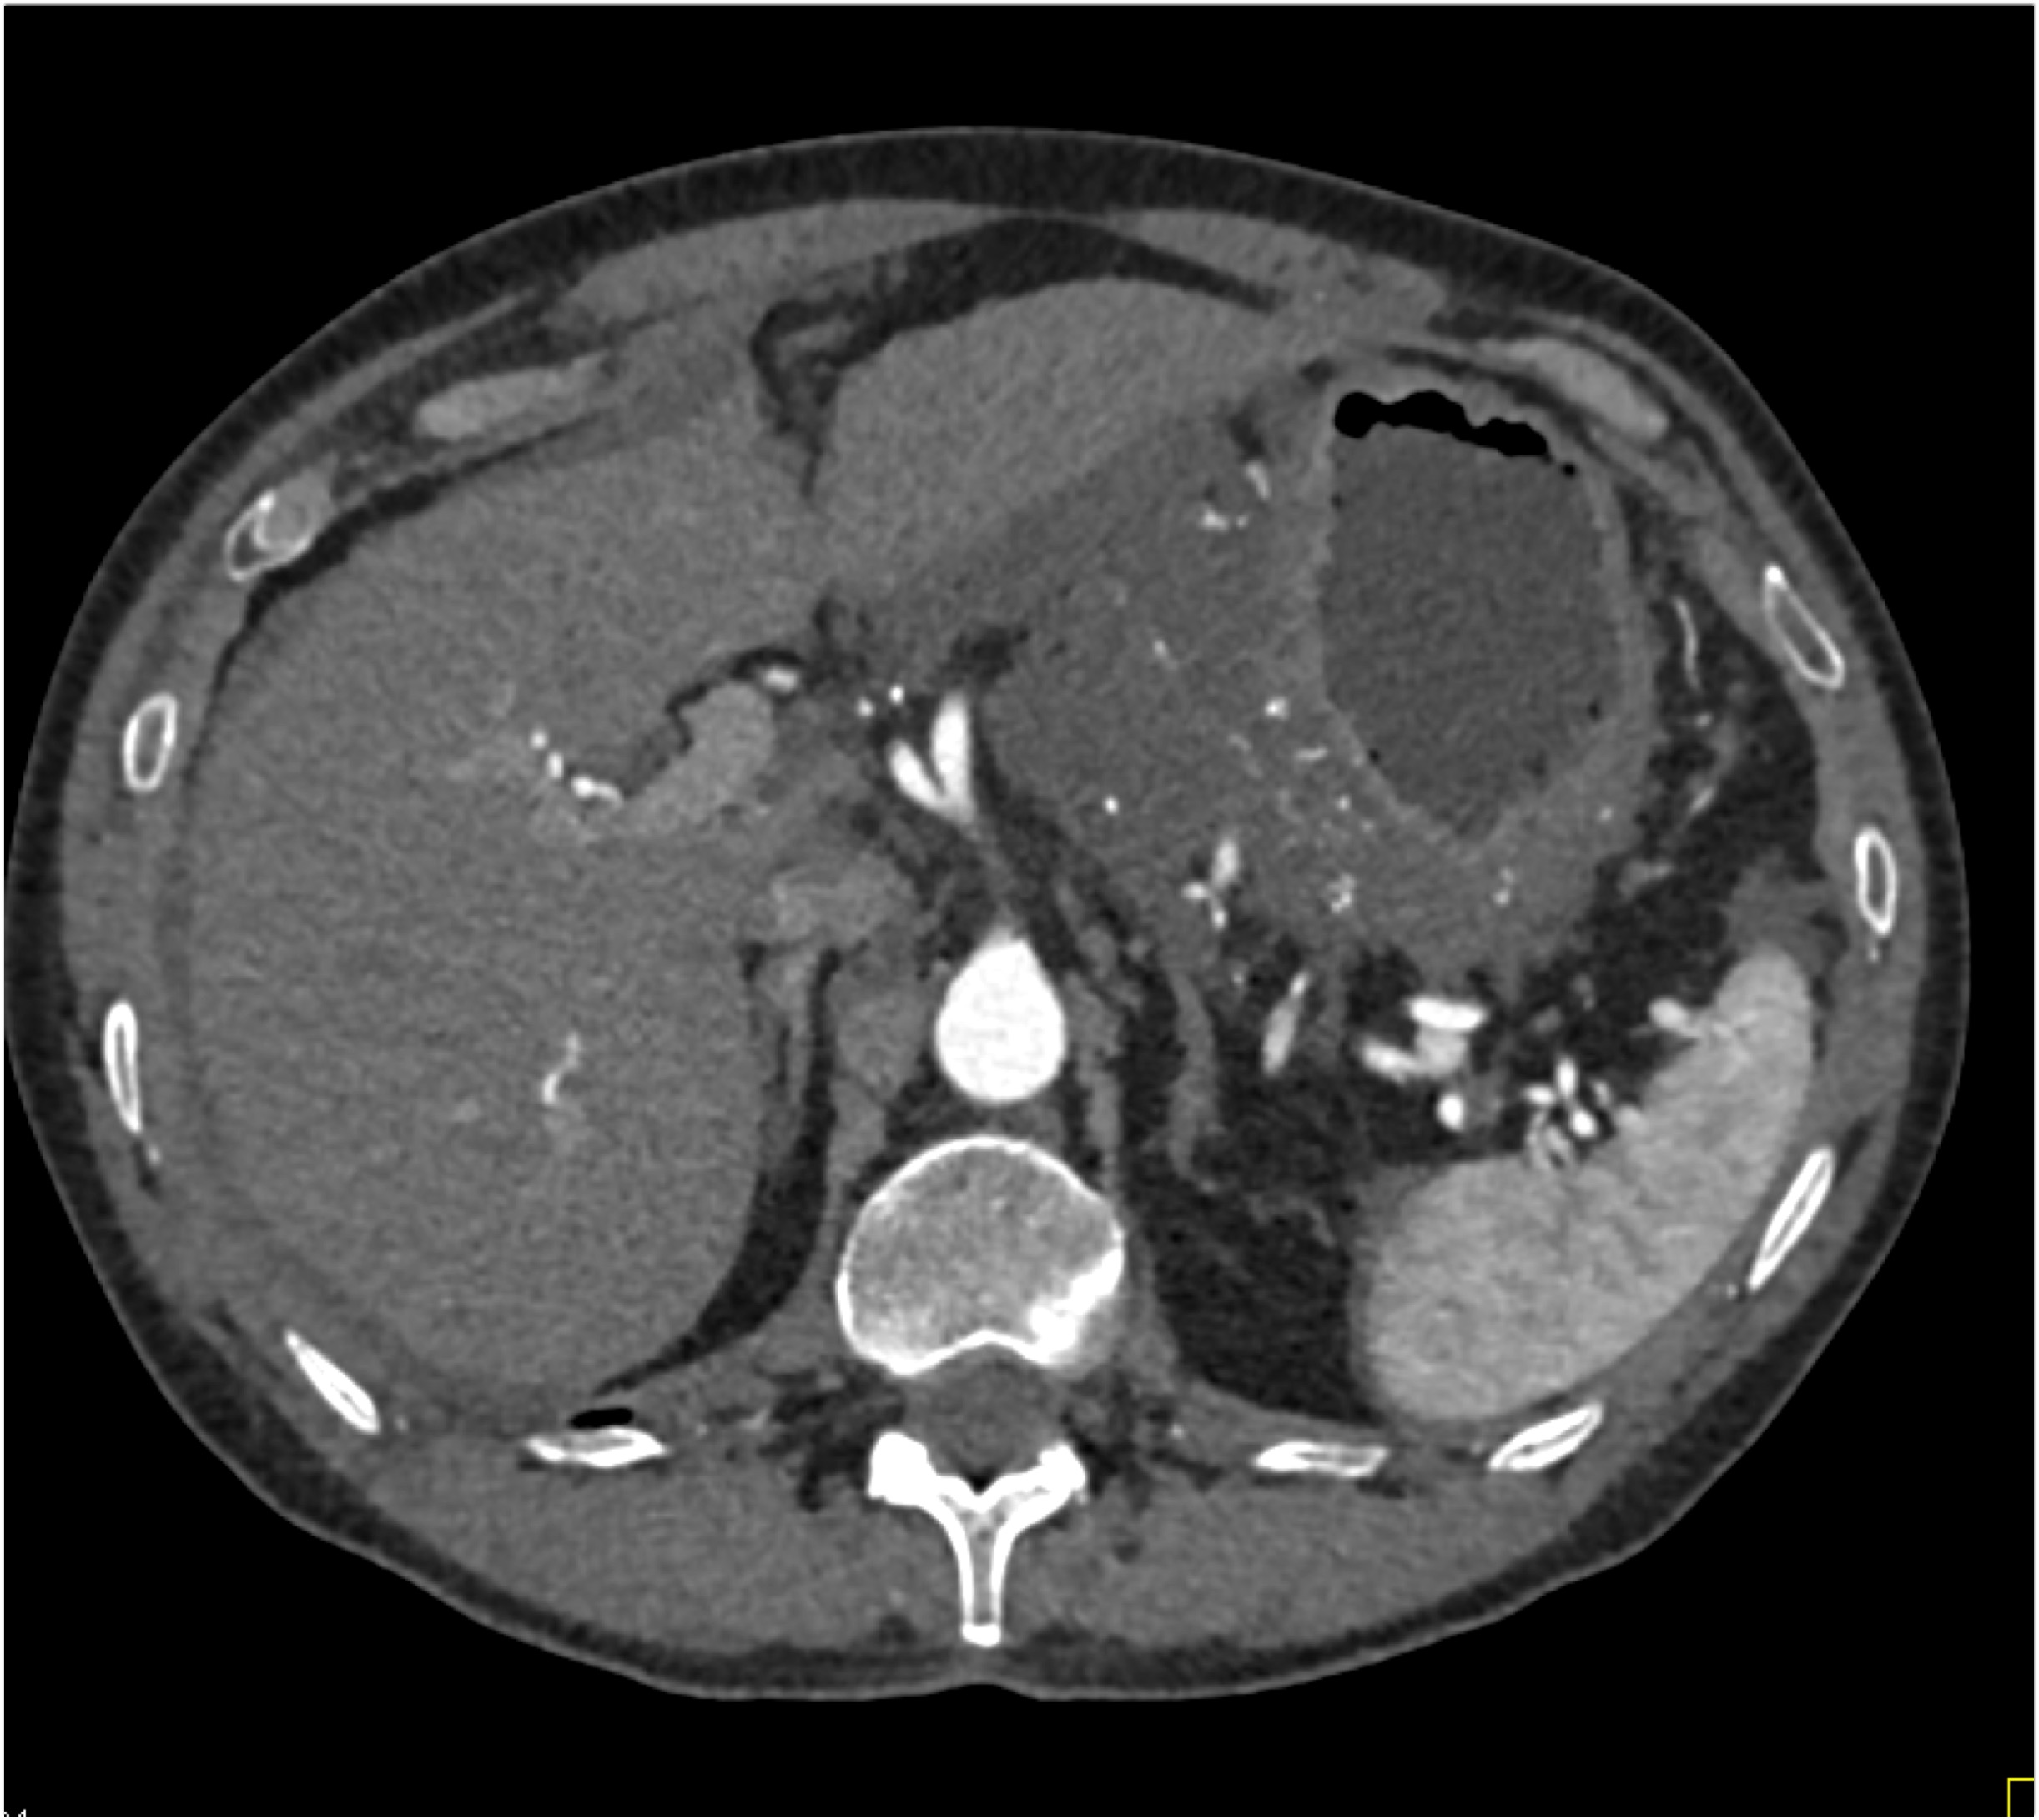

5) The most likely diagnosis in this case is?

adrenal carcinoma

pheochromocytoma

metastases to the adrenal

primary adrenal lymphoma